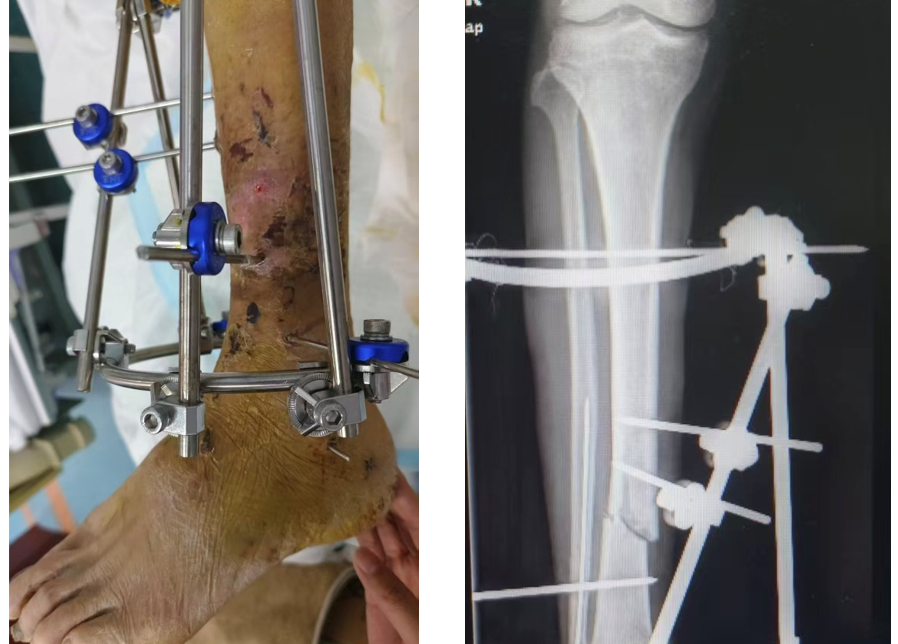

骨折外固定架固定術是一種通過體外裝置連接骨折斷端、維持骨穩定的手術方式。適用于開放性骨折、嚴重軟組織損傷或感染風險較高的骨折及需要骨延長或肢體矯形的患者。其特點是創傷小、操作靈活,且便于術后調整和護理,是復雜骨折救治的重要手段。

臨床中,許多外固定架固定的患者需要長期佩戴外固定架,長達數月至1年以上。有些患者回到家中不知道如何護理外固定架,從而導致患者釘道感染,甚至骨髓炎。骨折延遲愈合或者不愈合等問題。如何做好居家外固定架的護理,如何避免不必要的并發癥發生,是醫護人員需要指導患者在出院前必須掌握的技能。